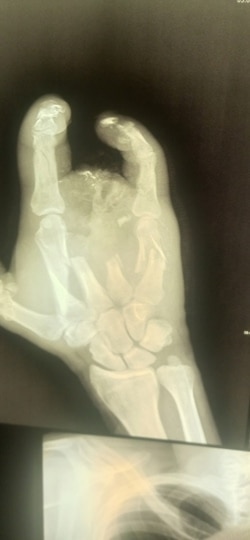

– Как меня вытащили, как везли до полевого госпиталя – не помню ни черта. Очнулся, узнал, что получил осколочное ранение, обжег шею, глаз, невзрывное осколочное ранение оторвало мне полруки, снесло все пальцы, разгромило всю кисть. Увезли меня в Луганск, там позволили три недели полежать, и все. Выпнули из военного госпиталя в обычную больницу. Я еще удивился, зачем на последние пять дней. Потом узнал.

Рука Алексея после ранения на войне

Оказалось, что с незажившими ранами покалеченного солдата отправили в гражданское медучредждение для того, чтобы на руках у него не было документов из военного госпиталя. И сейчас Алексей не может доказать, что стал калекой в бою.